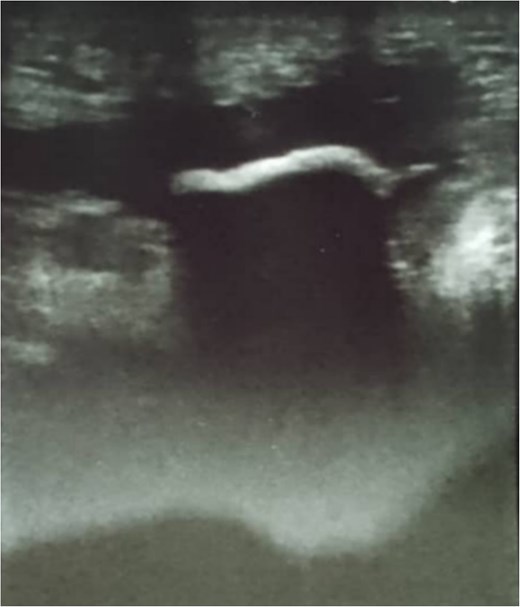

A 67-year-old male, with a smoking history of 40 pack-years, presented to the emergency department with an enterocutanous fistula. His medical history includes a prior laparotomy due to a gunshot wound, followed 6 months later by the development of an incisional hernia requiring surgical repair with the placement of a mesh patch. After 36 years of hernia repair operation, he developed an abscess, which was subsequently diagnosed and drained in another hospital. Three months post abscess drainage, the patient developed an enterocutanous fistula. On clinical examination, he exhibited grade II exertional dyspnea, orthopnea, and nocturnal paroxysmal dyspnea, with diminished breath sounds but no chest pain. Laboratory tests revealed normal urea and creatinine levels, mild anemia with a hemoglobin level of 10.8 g/dl, and elevated C-reactive protein at 150.4 mg/dl. Echocardiography and electrocardiography were both normal. A superficial abdominal ultrasound (US) detected a hyperechoic lesion with posterior acoustic shadowing extending 2 cm at the fistula opening, preventing clear visualization of any abdominal cavity connection. Moderate grade II edema was noted around the fistula opening in the subcutaneous tissue, without clear abscess formation (Fig. 1). A computed tomography (CT) scan was performed; the abdominopelvic CT scan findings indicate post-surgical changes in the abdominal region, including edema and air collections at the surgical site, without an assessment of an enterocutanous fistula. Chest CT findings were unremarkable, with no evidence of mediastinal lymphadenopathy. The heart and great vessels were of normal size (Fig. 2). Following a cardiology consultation confirming that surgical intervention was safe based on the patient’s normal laboratory parameters, an exploratory laparotomy was performed via a midline incision extending both above and below the umbilicus. The incision was carefully deepened through the abdominal wall into the peritoneal cavity. Initial exploration revealed a colocutaneous fistula; tracing the fistulous tract demonstrated that it terminated at the sigmoid colon. Further inspection uncovered a migrated surgical mesh that was wrapped and strongly adherent to the sigmoid colon. With considerable difficulty and utmost care, the displaced mesh was excised along with the resection of ~4 cm of the sigmoid colon. An end-to-end anastomosis of the sigmoid colon was then performed. Additionally, two tubular surgical drains were placed—one in the Douglas pouch and another at the splenic flexure of the colon—to facilitate post-operative drainage. Hemostasis was achieved with thorough drying, followed by layered closure of the wound after proper disinfection, and the application of a sterile dressing (Fig. 3). Following surgery, the patient was prescribed a regimen including antibiotics— ceftriaxone at 1 g twice daily and metronidazole at 500 mg three times daily—to manage infection risk. Intravenous paracetamol was administered every 8 hours for pain control. The patient was discharged in stable condition two days after surgery and a follow-up period of 6 months indicated no further complications.

Superficial abdominal ultrasound showing a hyperechoic lesion with posterior acoustic shadowing extending 2 cm at the fistula opening, limiting visualization of any abdominal cavity connection. Moderate grade II edema is seen in the surrounding subcutaneous tissue, with no clear abscess formation.